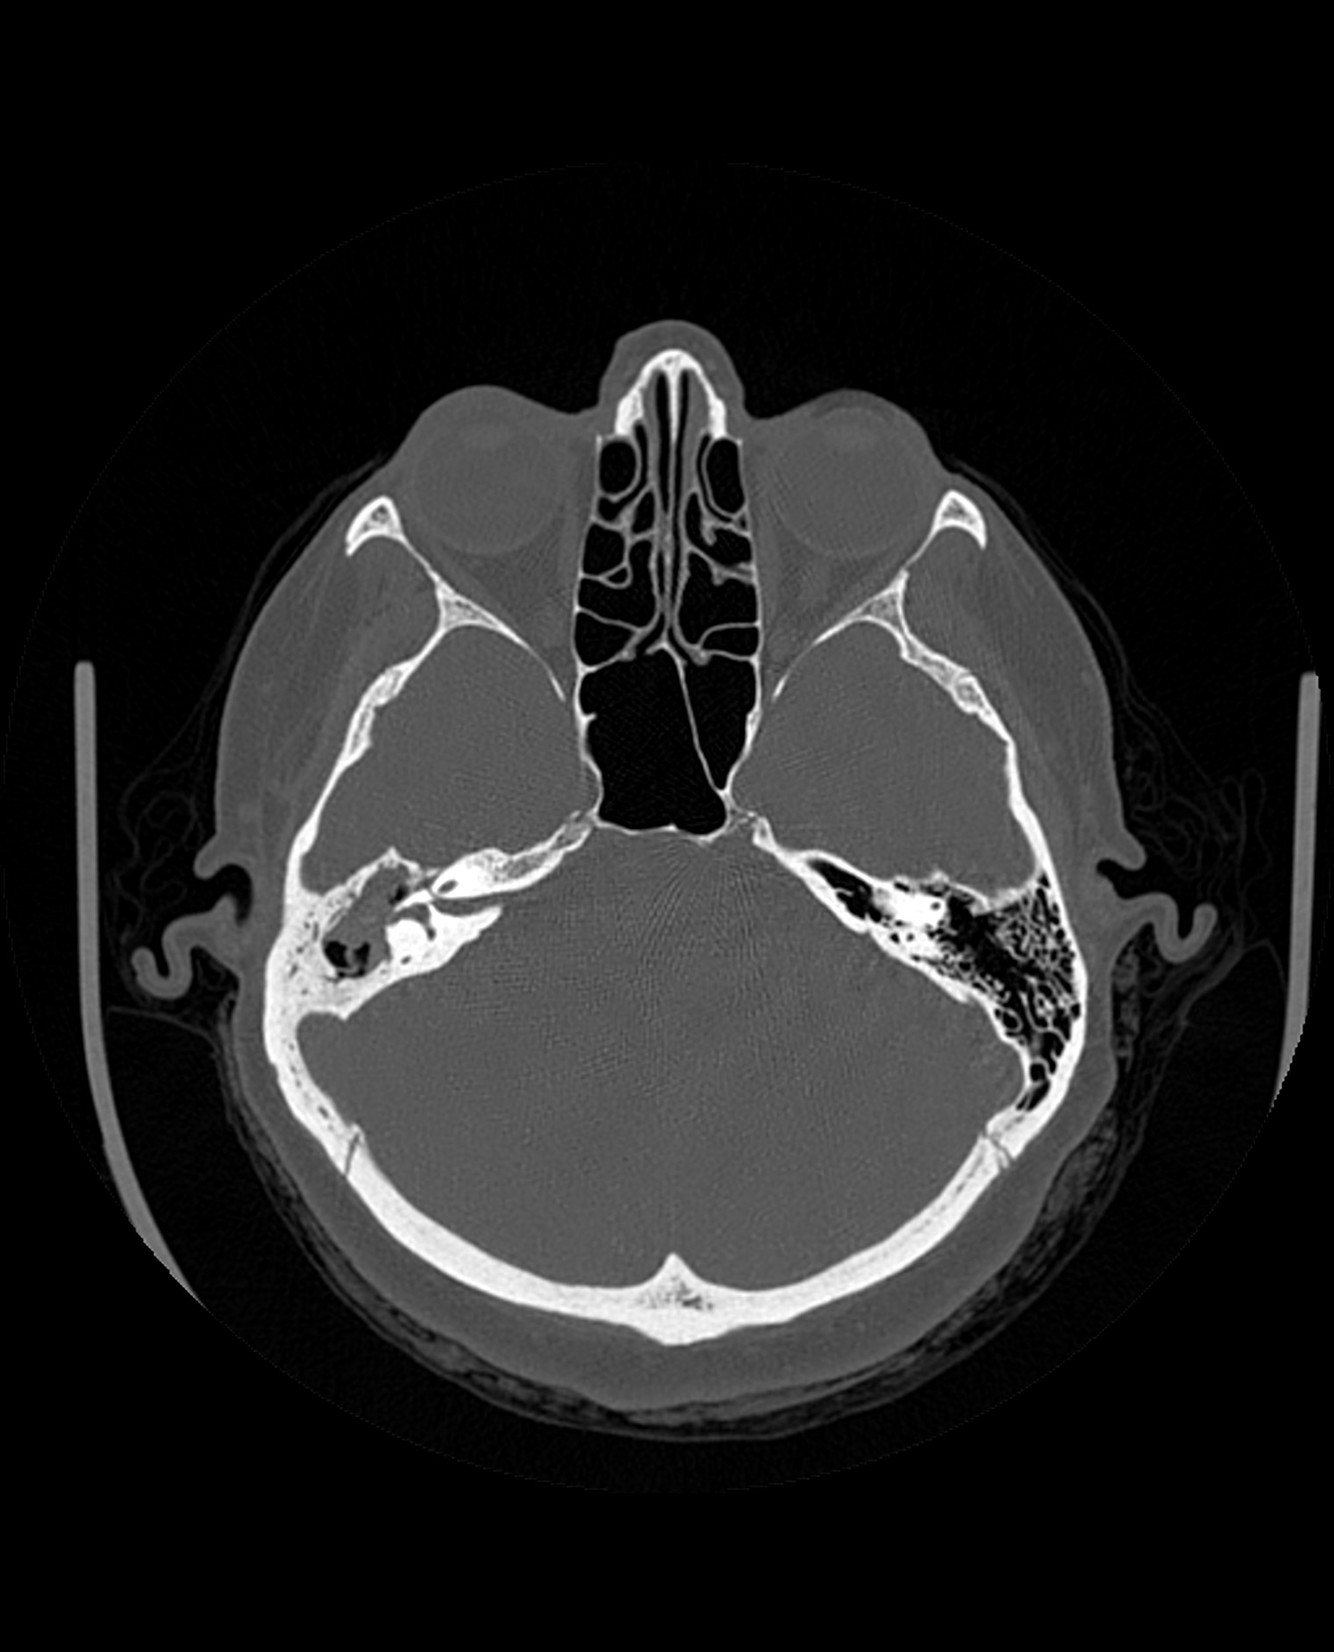

What are the complications of Acquired Cholesteatoma?

What complication/s are demonstrated here?

Automastoidectomy denotes extensive bone destruction of the mastoid mimicking the appearance of surgery (mastoidectomy), most often caused by cholesteatoma.

Spontaneous evacuation of cholesteatoma can be seen with automastoidectomy 1. In these circumstances, it is often referred to as mural cholesteatoma or unusual cholesteatoma shell, as there is no residual soft tissue mass 2.

Automastoidectomy has also been reported with keratosis obturans 3.

Automastoidectomy refers to extensive bony destruction of the mastoid forming one cavity resembling operative mastoidectomy. Cholesteatoma is the most common cause and this subtype is known as “mural cholesteatoma”.

Labyrinthine fistula refers to abnormal communication between inner ear perilymph and middle ear cavity on top of erosion or fracture of the bony labyrinth.